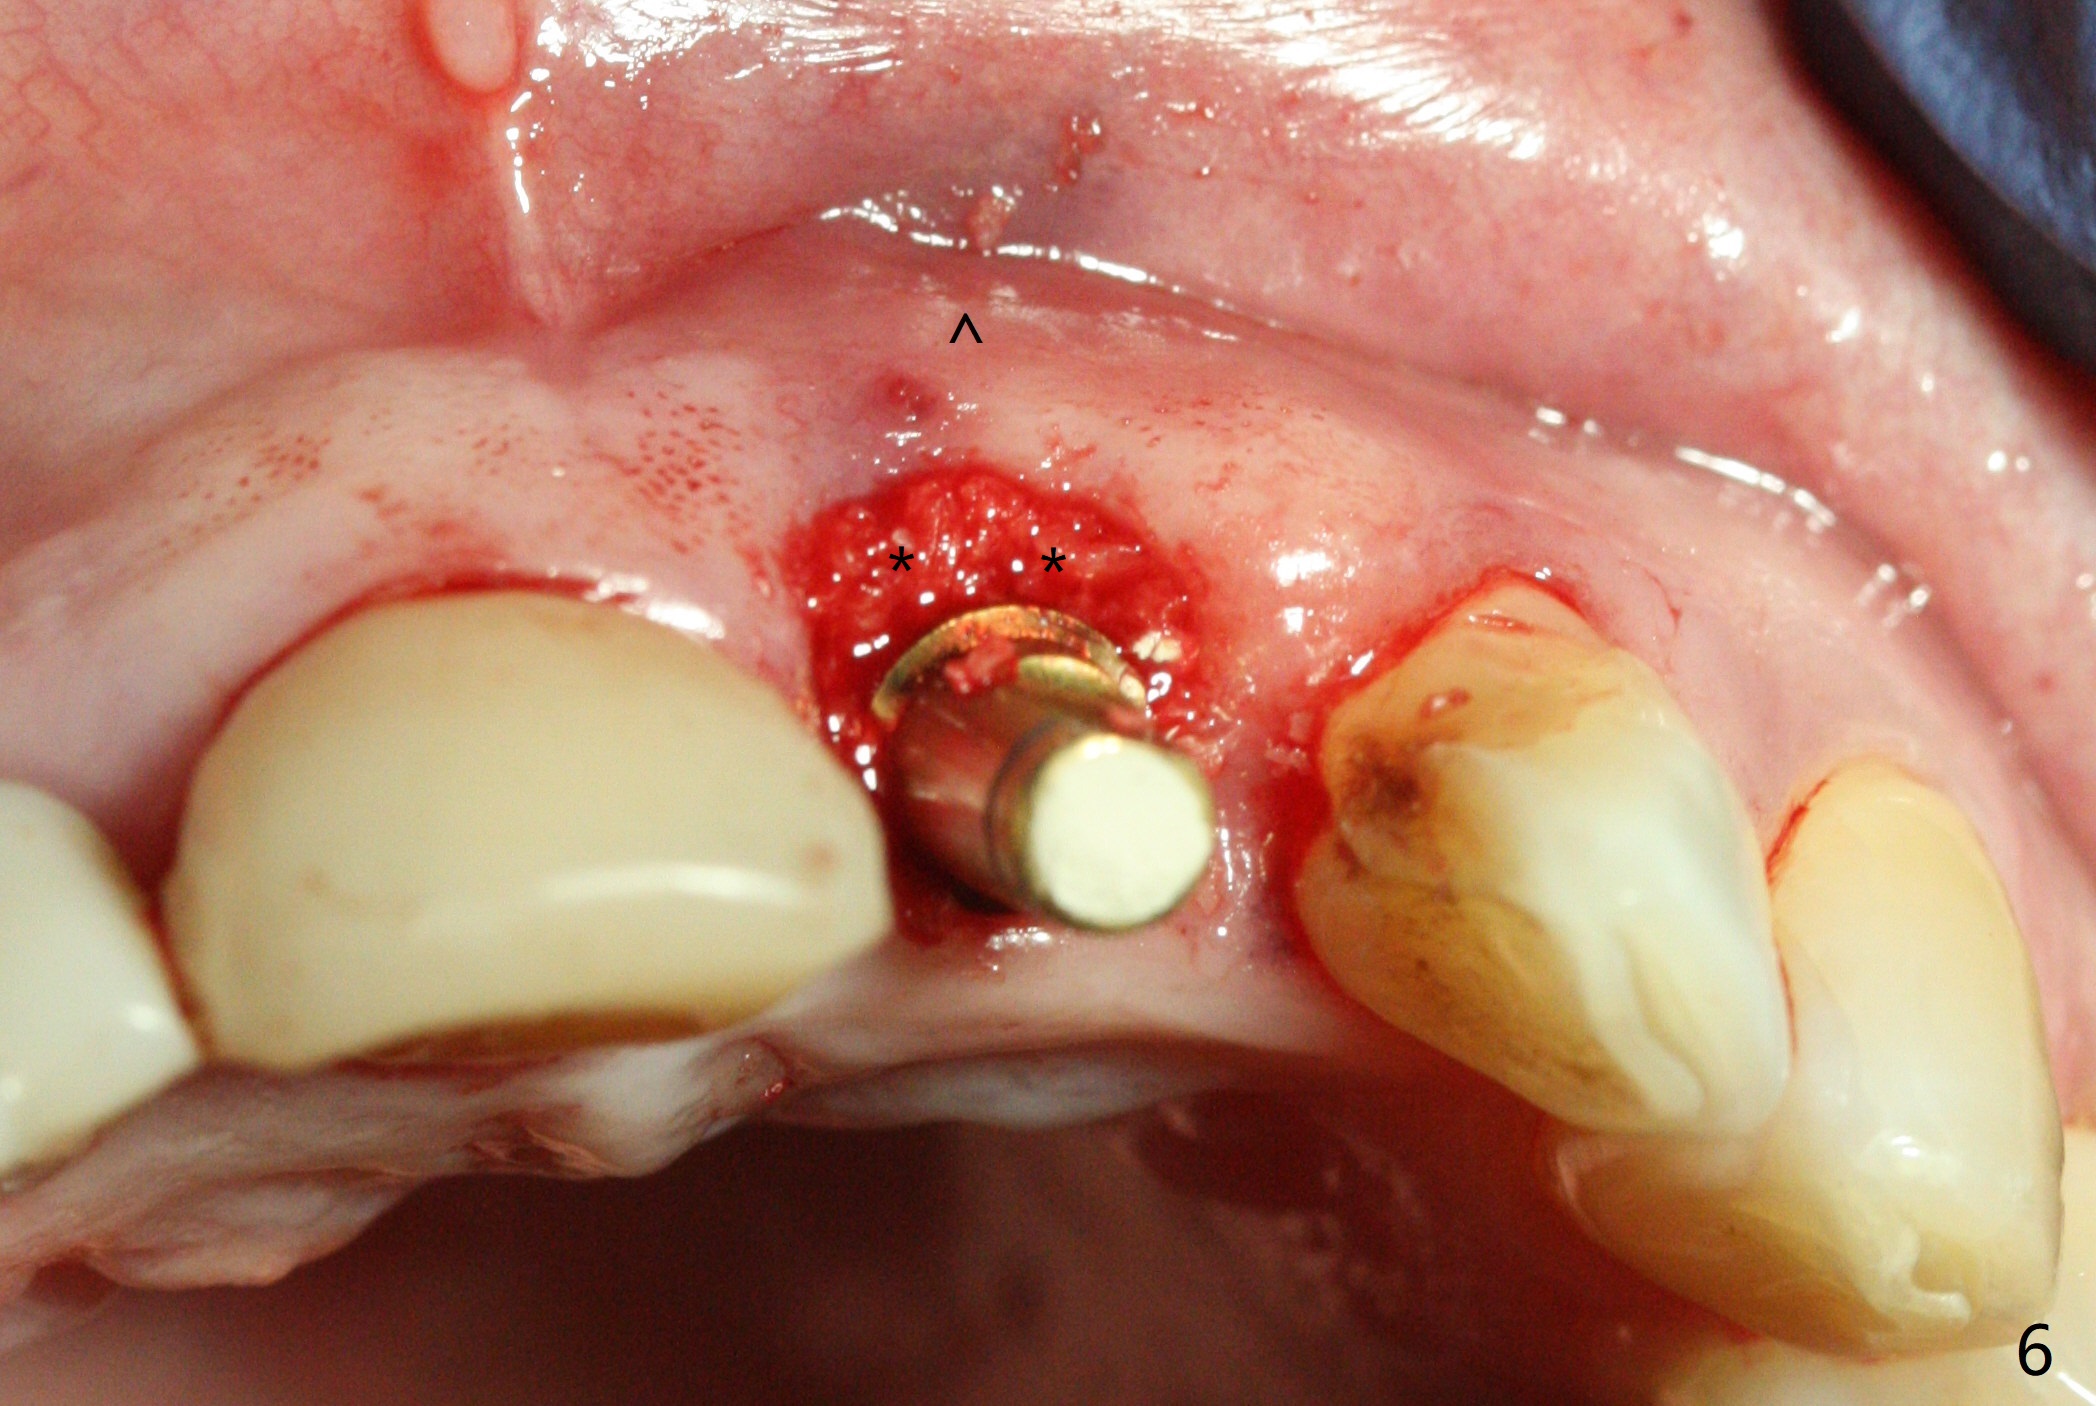

In spite of the incisobuccal shift of the tooth #9 with gingival recession (Fig.1) and loss of the buccal plate (intraop finding), there is no buccal contour collapse (Fig.2 *), due to the presence of the buccal bone of the neighboring teeth and the root of the affected tooth. After extraction, osteotomy (Fig.3) and dummy implant try in (Fig.4), a definitive implant is placed palatally with the buccal gap (Fig.5 *). In fact there is mild buccal contour collapse prior to bone graft (Fig.5 arrow). When allograft (Vera, Fig.6,7 *) is packed buccal to the implant and overlying abutment as a solid support, the buccal contour seemingly returns normal (Fig.6 arrowhead). An immediate provisional is fabricated to prevent loss of the bone graft during healing period. Bone graft kept in place by the provisional turns yellow 6 days postop (Fig.8). The buccal plate remains strong, while the fistula becomes indistinguishable. After adjustment of the provisional margin a few times (nearly 3 months postop, Fig.9,10), the gingival margin appears to have grown incisally, as compared to Fig.1. There is minimal buccal bone collapse (Fig.10). Dislodgement of the abutment and provisional forces her to return 1 year 4 months postop; the socket has healed (Fig.11). The buccal plate is not concave 1 year 4 months postop (Fig.12). The gingiva is slightly recessive (Fig.13) with mild buccal plate concavity (Fig.14) immediately before cementation. The implant could be placed ~ 1 mm deeper (Fig.15).